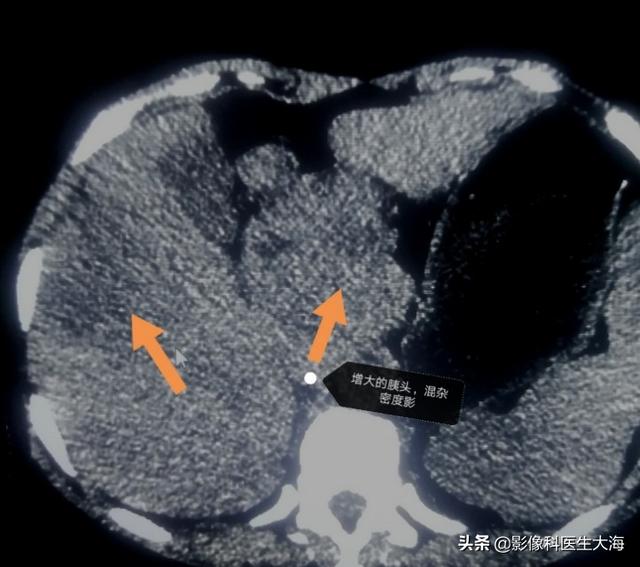

Enfin, et ce n'est pas le moins important, le fait d'être dans un environnement où les fumées lourdes sont présentes depuis longtemps contient des gaz produits après la combustion du gaz naturel et du gaz de pétrole liquéfié, et ces gaz contiennent des substances cancérigènes, qui peuvent facilement conduire à une incidence élevée de cancer du foie. L'oncle d'un de mes collègues est un chef cuisinier qui a longtemps travaillé dans un environnement exposé aux fumées lourdes. Il vient d'apprendre que son cancer du foie s'est métastasé à la tête du pancréas à l'aube de la cinquantaine et qu'il n'a pas survécu plus de trois mois.